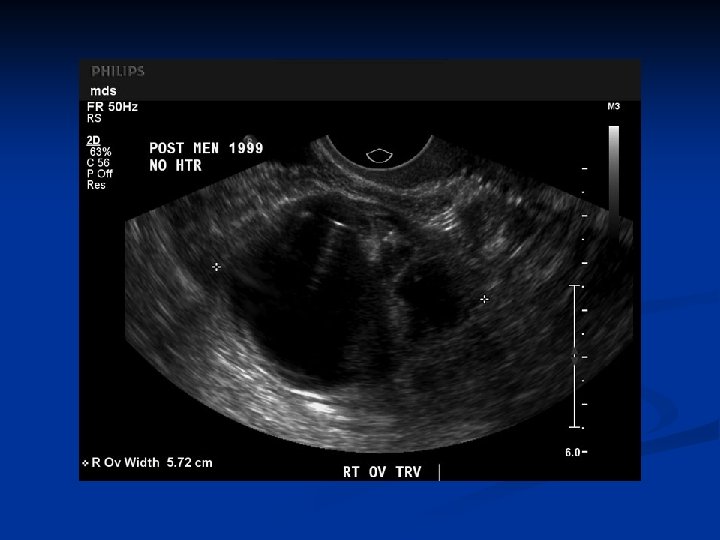

Physiologic Enlargement n Hypertecosis n n No gross enlargement of the ovary Lesions are demonstrated only by histologically In premenopausal women is associated with virilisation, and clinical findings similar to PCO n n n Characterized by persistent anovulation Enlarged ovaries Sec amenorrhea Oligomenorrhea Infertility

Physiologic Enlargement n n n Prevalance is 5 -10% 50% of patients are hirsute, 30 -75% are obese Lipid anomalies, insulin resistance, increased LH/FSH ratio